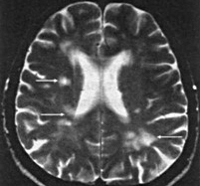

I63.9 Инфаркт мозга неуточненный